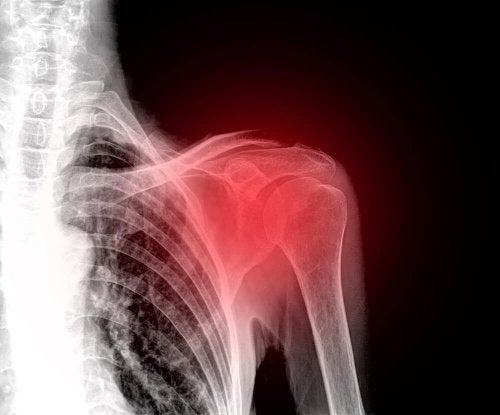

Ruptura de coafă rotatorie constituie o leziune care afectează frecvent umerii persoanelor de vârstă mijlocie. Drept consecință, se numără printre principalele cauze ale durerii de umăr.

Coafa rotatorie reprezintă un grup de mușchi și tendoane care se învecinează cu oasele umerilor. Aceasta este responsabilă de menținerea stabilității articulare și executarea corectă a mișcărilor.

Simptomele rupturii de coafă rotatorie depind de severitatea leziunii. Cel mai predominant simptom este reprezentat de durerile de umăr și. În plus, toate mișcările articulației afectate sunt limitate.